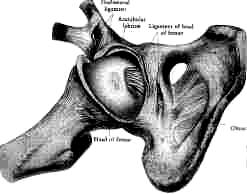

Organic correlations. Teleological aspect of the phenomenon. Adaptation to future events. Adaptation to haemorrhage. Correlation of the structures of the eye